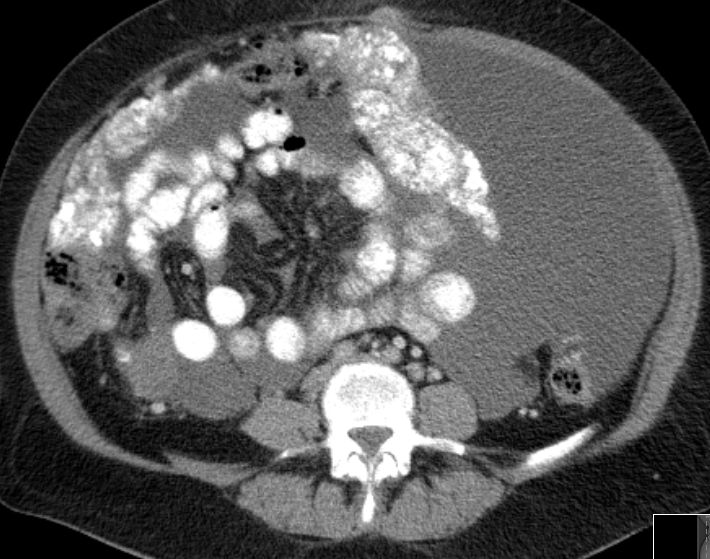

6 Monate später Lebermetastasen.![]() |